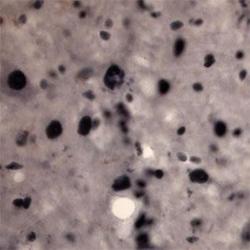

Immunohistochemistry

NB110-75039 IHC

Method:

Other validation